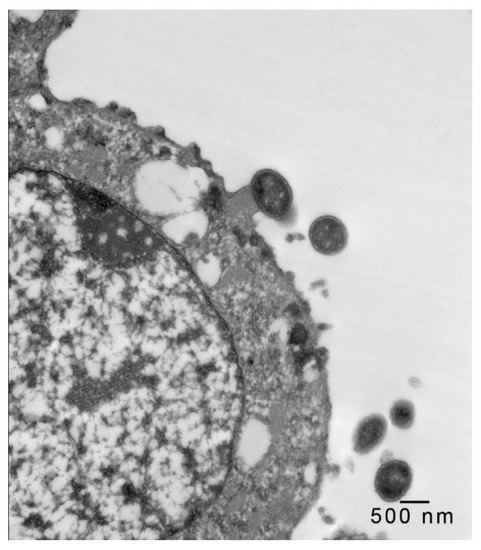

In 1-μm thick Araldite sections of urinary bladder prepared from tissues originally contained within the paraffin blocks [25], bacteria were detected only in piglet 15627 (Figure 1). In this piglet, in which bladder sections were oriented such that all three cell layers (basal, intermediate and superficial or umbrella) of the urothelium [26,27,28,29] were visible, bacteria, corresponding to bovine-origin strain 2891, were diffusely adherent to the apical surfaces of umbrella cells. By TEM, bacterial cells were found intimately attached to pedestals (Figure 2, Figure 3 and Figure 4). Some bacterial cells appeared to be attached to microplicae, preceding pedestal formation (Figure 4).

Figure 3.

Transmission electron photomicrograph of a thin section of a superficial epithelial (umbrella) cell of the urinary bladder of piglet 15627, 8 days PI with bovine-origin strain 2891. High magnification of the bacterium intimately attached to an actin pedestal in the previous figure. Bar = 100 nm.

Morphologically, the pedestals to which bacteria in the urinary bladder of piglet 15627 were intimately attached were consistent with actin pedestals induced by EHEC and enteropathogenic E. coli (EPEC) in intestinal epithelium [24]. To our knowledge, this is the first report of intimate bacterial adherence and actin pedestals in the uroepithelium in any species. Staley et al. [30] first reported these lesions in 1969, describing them as attachment and microvillous exfoliation in ileal enterocytes of newborn, cesarean-derived piglets intragastrically inoculated with an E. coli strain belonging to a classical EPEC serotype, O55:H7. Takeuchi et al. [31] later described these lesions as occurring in rabbits inoculated with RDEC-1, a rabbit-origin O15:NM E. coli later classified as an EPEC [23]. Soon thereafter, the lesions were recognized in human infants with EPEC infection [32,33]. Moon et al. coined the term “attaching and effacing” to describe intimate attachment and effacement of microvilli in the intestinal epithelium of piglets and rabbits by EPEC [23]. Knutton et al. [34] first determined that the electron-dense material underlying the bacteria within the pedestals was filamentous actin. Over the past 50 years since the initial report by Staley et al. [30], numerous studies, many at the molecular level, have elucidated key bacterial and host factors involved in the pathogenesis of intimate attachment and pedestal formation [29].